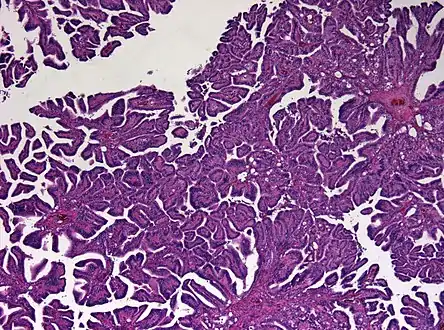

The tumor is neuroectodermal in origin and similar in structure to a normal choroid plexus. They may be created by epithelial cells of the choroid plexus.

Micrograph of a choroid plexus papilloma. H&E stain.

Plexuspapillom Overview